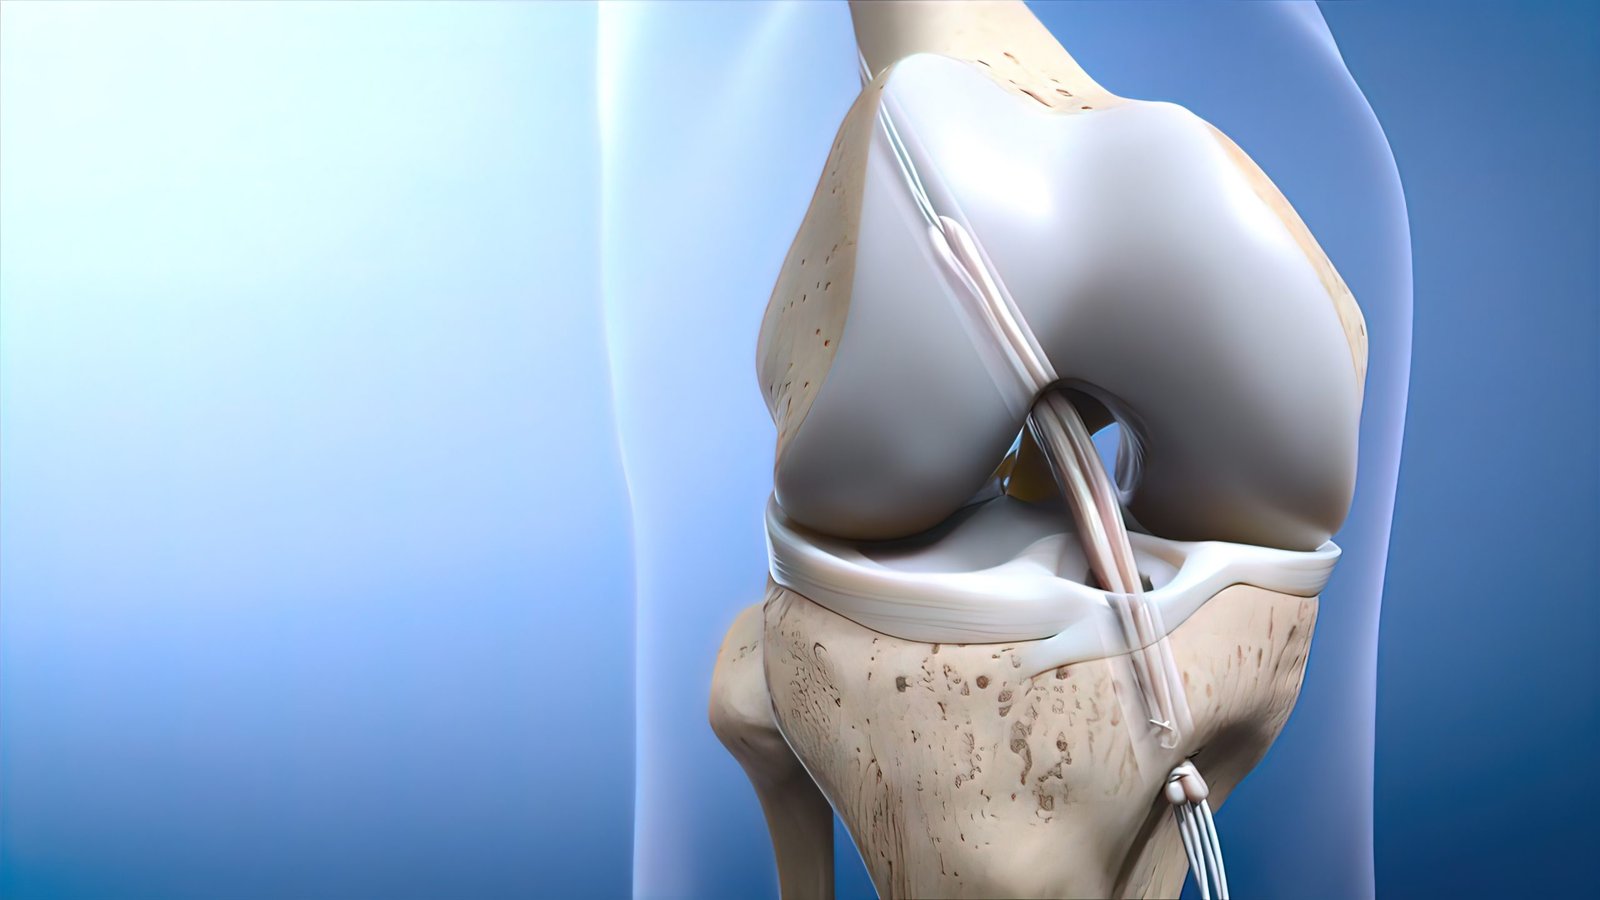

Minimally Invasive Precision: Benefit from our minimally invasive arthroscopic approach, minimizing tissue damage and promoting faster recovery compared to traditional surgery.

Expert Surgeons: Our skilled orthopedic surgeons specialize in ACL reconstruction, utilizing advanced techniques and state-of-the-art equipment for optimal results.